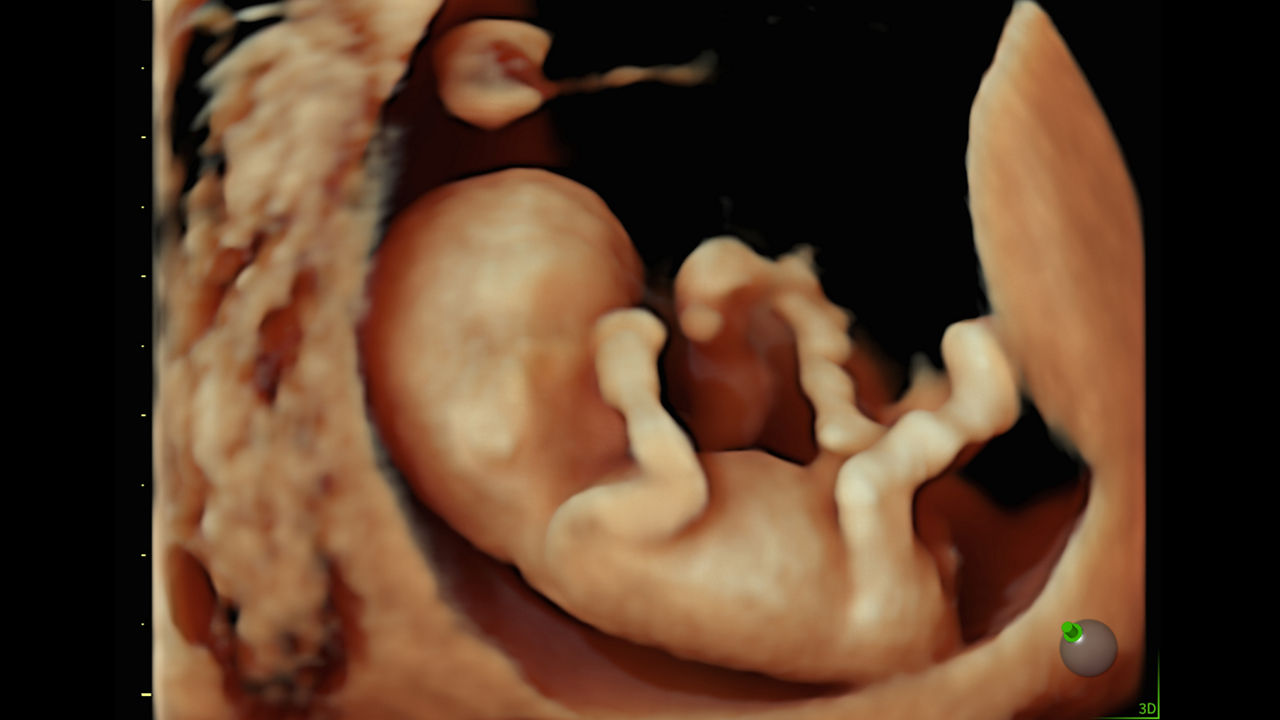

Image quality

Excellent images that are easy to acquire

Image quality is everything in ultrasound

The Voluson Performance 18 delivers high-resolution, detailed imaging with one-touch optimization for effortless scanning—helping you deliver quick, confident answers across a wide range of patient.